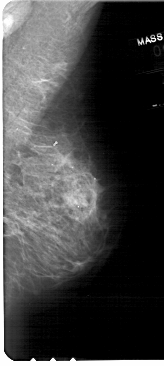

A_1730_1.RIGHT_MLO

RIGHT_CC LINES 4981 PIXELS_PER_LINE 2326 BITS_PER_PIXEL 12 RESOLUTION 43.5 NON_OVERLAY

RIGHT_MLO LINES 5476 PIXELS_PER_LINE 2446 BITS_PER_PIXEL 12 RESOLUTION 43.5 NON_OVERLAY